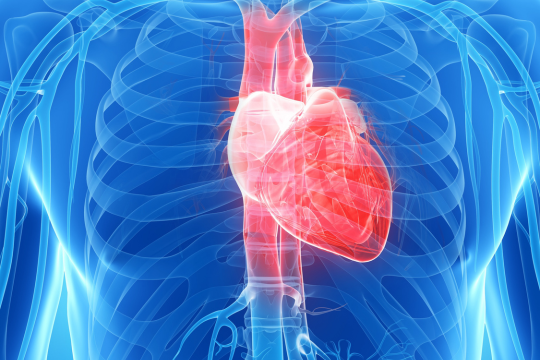

Protecting transplant patients and saving lives

Immunity at the heart of the matter

Detecting a silent threat – transplant rejection

Optimising outcomes for kidney transplant patients